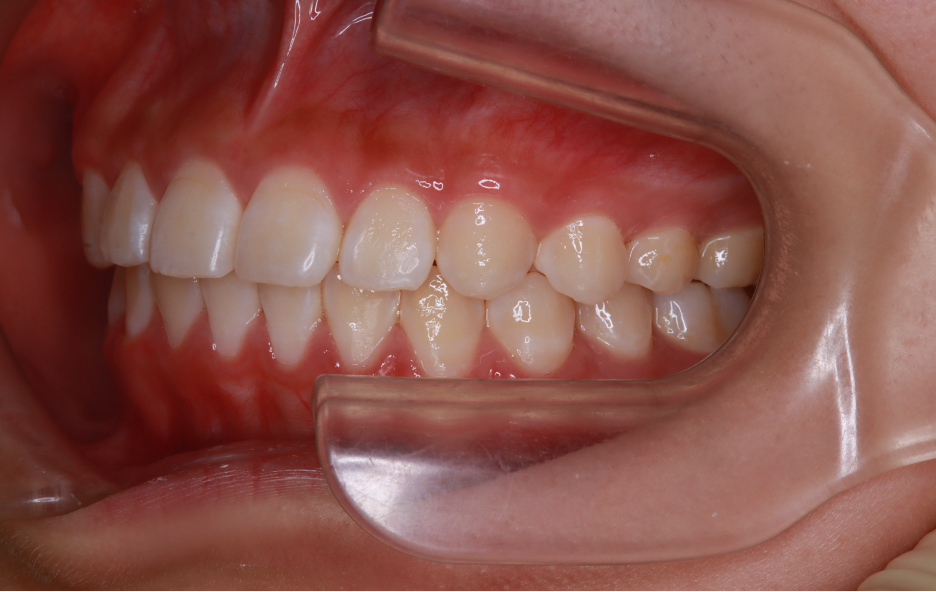

After